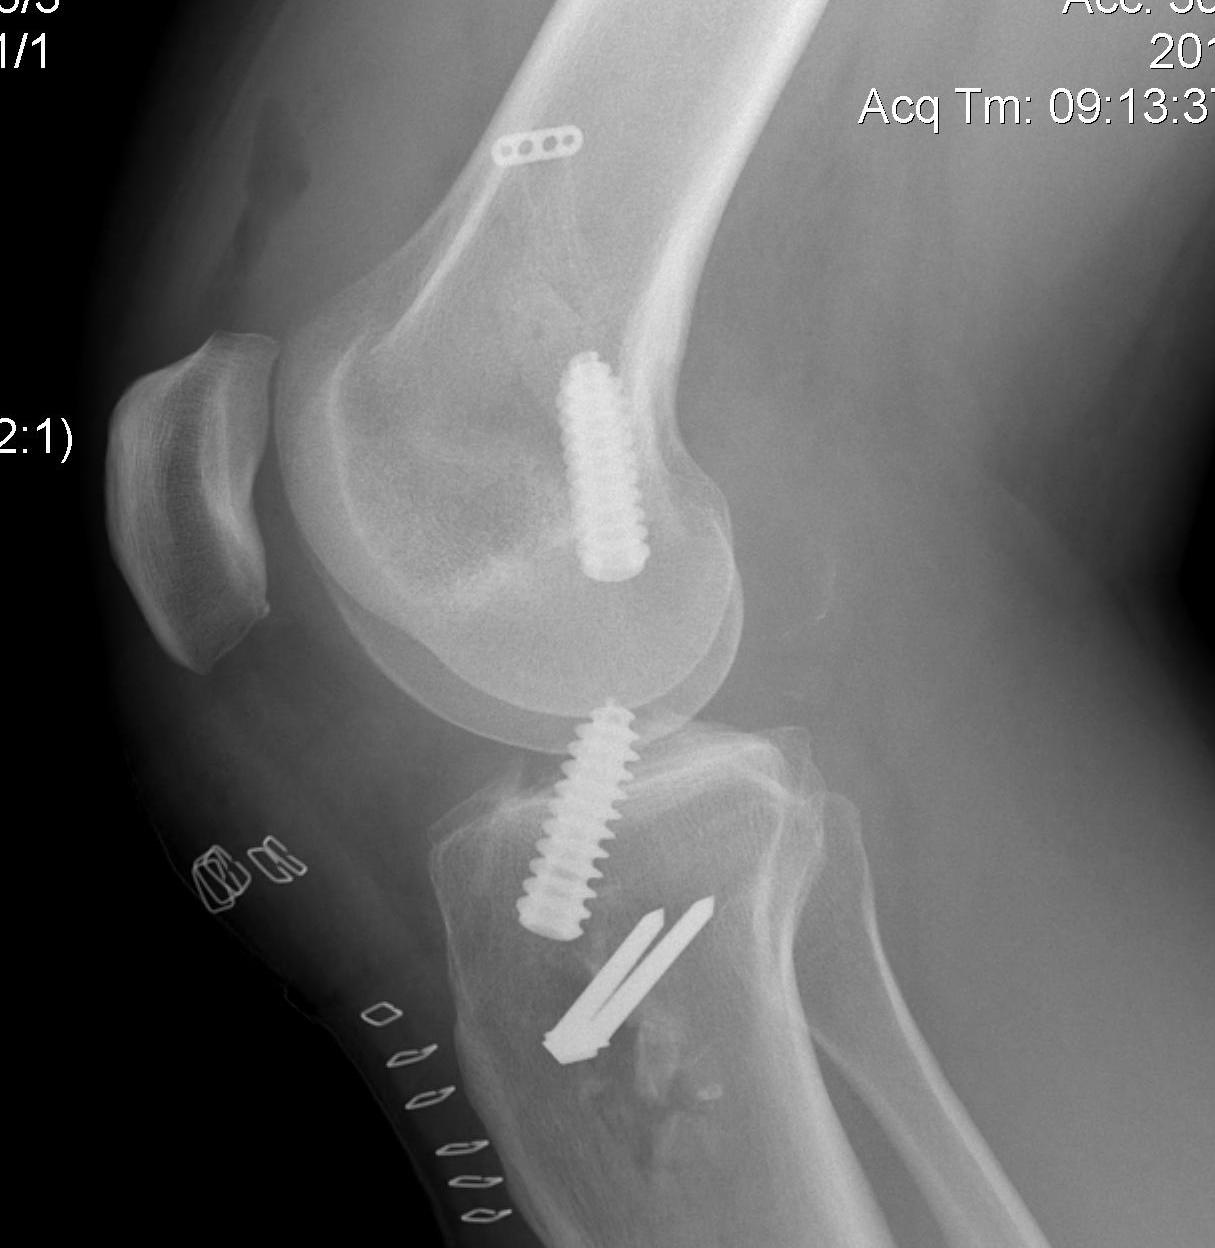

Achilles allograft used, and 12 mm x 20 mm bone plug used in femoral side. Both tunnels drilled where indicated.

Tibial screw ignored, old femoral tunnel ignored. 12 mm tunnels drilled.

Old staple had to be removed. Graft passed and fixed on femoral side with 9 x 25 mm screw.

Achilles tendon fixed on tibial side with 9 x 25 screw

Tibial bone very poor and screw little bite (advanced very easily too far into tibia, but not seen in joint).

New staple used, but had to be repositioned as cortical bone soft and fracture easily.